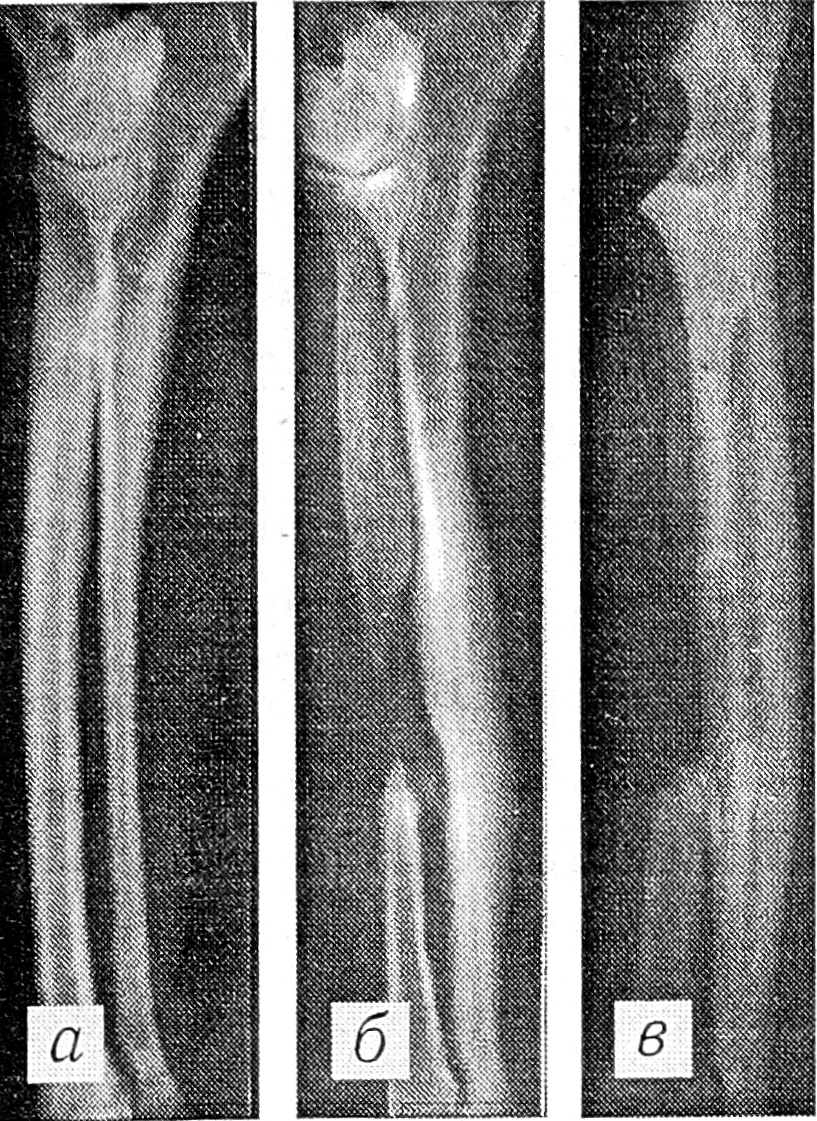

Рис. 2. Гиперостоз от перенапряжения: рентгенограммы локтевой кости до (а), через 130 (б) и 845 (в) сут функциональной перегрузки.

В первые 1—1,5 мес функциональной перегрузки происходит быстрое увеличение толщины самого тонкого участка диафиза локтевой кости. Со 2-го месяца это увеличение замедляется за счет физиологической перестройки и распространяется на всю кость (рис. 2).

Корреляционный анализ зависимости степени утолщения локтевой кости от исходного индекса ее массивности выявил сильную отрицательную связь (г = -0,74), т.е. чем ниже индекс массивности этой кости был до перегрузки, тем выше степень ее утолщения. Уравнение линейной регрессии имеет вид:

х2 = (-5,72+0,99) х1+ 367,83,

где — исходный индекс массивности локтевой кости, х2 — степень утолщения этой кости вследствие функциональной перегрузки (в процентах).

Эти расчеты позволяют прогнозировать степень утолщения кости с погрешностью, близкой к 2,5%. Уравнение имеет достоверный коэффициент регрессии (r = 5,80), являющийся статистически значимым при n — 30.